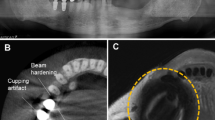

The two types of metal samples produced different amounts of the MD in the phantom. As shown in Fig. 4, the sagittal images of VIBE 5 shows bended grids near the signal-loss and pile-up artifact region. The color map represents the severity of the calculated metal-induced distortion with the scale bar on the right. With the stainless-steel bracket, the MD was above 1 mm for the VIBE5 sequence in the region of 4.0 to 4.8 cm from the center of the implant, or 1.6 to 2.4 cm from the boundary of the signal loss region. With the non-precious alloy crown-supported implant only 1.6 to 2.4 cm and 0.8 cm, respectively, were observed. With both sample materials the frequency direction (MD-F) was the predominantly affected direction (Fig. 4).

Sagittal view of VIBE 5 image with geometric distortion in color map: the sagittal images of VIBE 5 show bended grids near the signal-loss and pile-up artifact regions. The color map represents the severity of the calculated metal-induced distortion (MD) with the scale bar on the right. Left to Right: representative sagittal VIBE5 images with calculated metal-induced distortion in frequency-encoding/phase-encoding/slice direction (MD-F/P/S) and the total MD in Euclidean distances [mm].